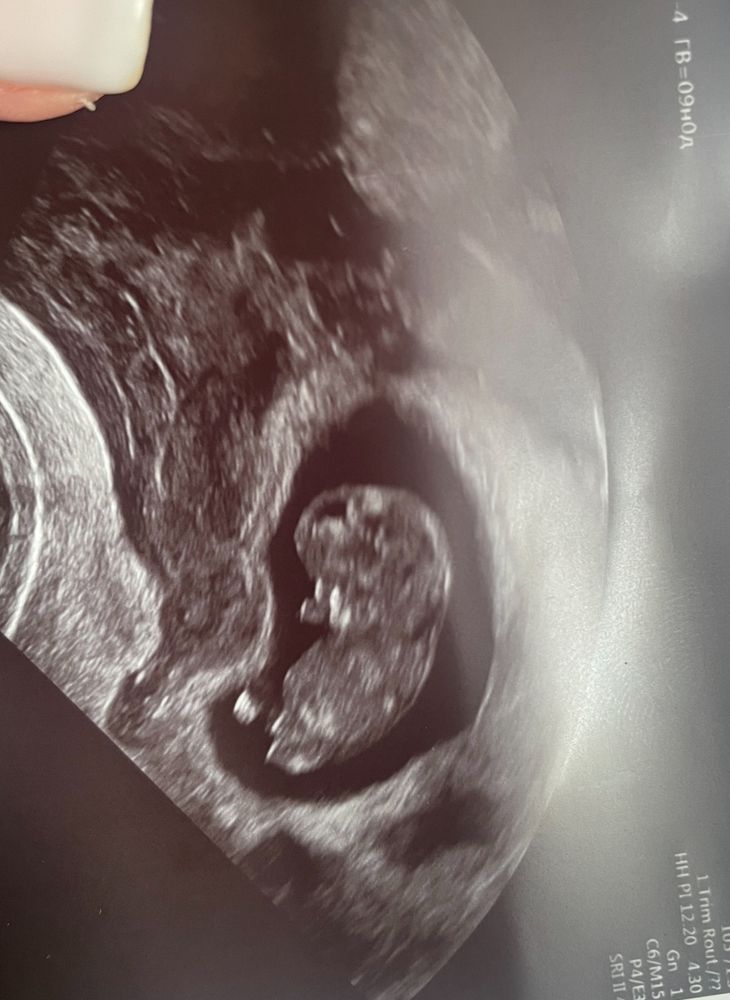

Ирина , вот мой малыш в 7,2 и в 9,0 , даже визуально ощущение, что плодное яйцо ему прям в притык. Но мне сказали, что в разных проекциях разный диаметр, главное, что плодное яйцо не деформировано

20.10.2024

Ответить